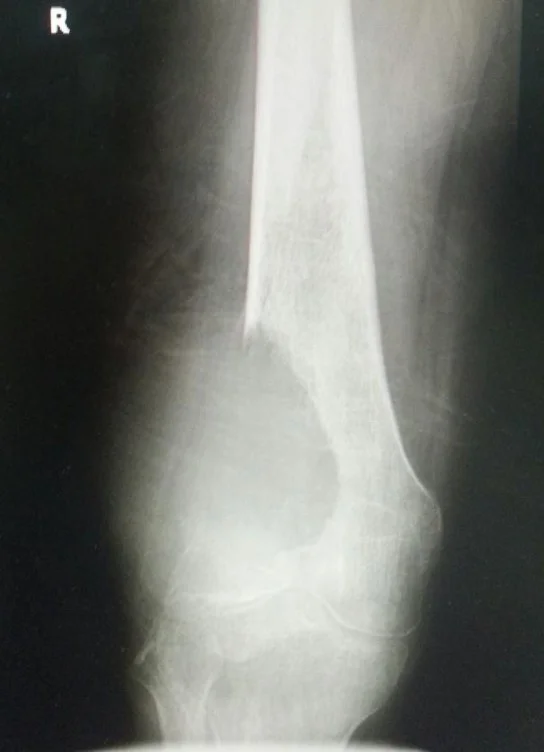

Trauma

- Trauma